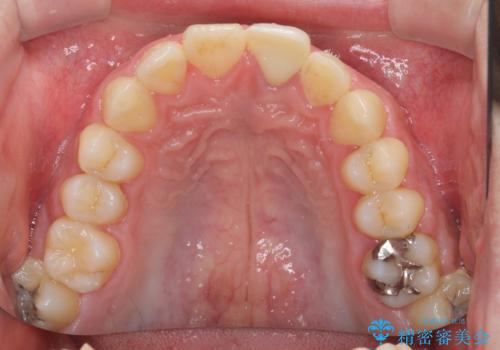

レントゲン写真より、歯の中の神経組織が失活していることが分かったため、根管治療、ファイバーコアによる土台築製を行い、オーダーメイドタイプのオールセラミッククラウンにて補綴することとしました。

人目を気にすることなく話ができるようになり、患者様には大変満足していただきました。